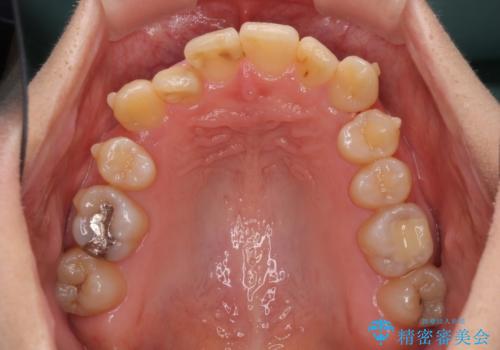

- 上下の八重歯を気にして来院された患者様です。

八重歯の後ろの歯を1歯抜歯し、補助装置(リンガルアーチ)を用いて八重歯の位置を改善し、その後インビザラインにより矯正治療を行うこととしました。

右側のみ上下小臼歯を抜歯したため、上下の正中が右にずれてしまう可能性があります。

また、元々右側は上下が咬み合っていないため、矯正をしても咬み合わないことも考えられました。

治療期間はかかりましたが、正中も合い、綺麗な仕上がりとなりました。